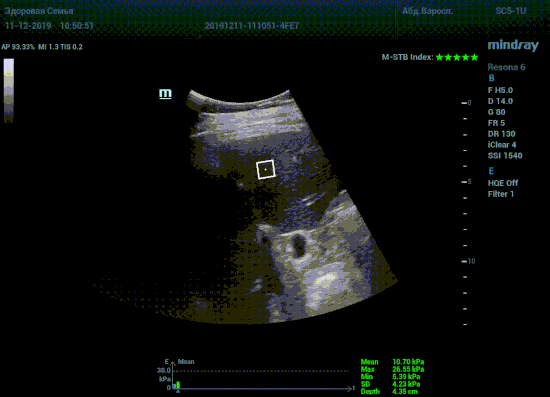

Что может дать ультразвуковое исследование печени помимо образований, гепатомегалии и цирроза? Диагностические системы, оснащенные функцией STQ (SoundTouchQuantification) имеют возможность регистрировать сдвиговые волны в паренхиме печени и оценить её эластичность. Такие возможности есть у систем серии Resona 6 и Resona 7 компании Mindray.

Датчик посылает ультразвуковую волну способную сжать участок паренхимы печени. В момент расправления тканей органа после сжатия, происходит образование поперечные волн. Для их регистрации, следом за волной сжатия, посылается регистрирующая волна, которая улавливает изменения скорости. Закономерность изменения скорости позволяет использовать модуль Юнга для оценки плотности ткани. Таким образом мы получаем аналог FibroScana’а, который упоминается в рекомендациях по диагностике и лечению жировой болезни печени, фиброза и цирроза. Разница в том, что теперь не нужно приобретать отдельный прибор. Все уже есть в ультразвуковой системе. Быстрее, дешевле, доступнее. Так же исчез пугающий пациента эффект «удара» типичный для фиброскана. Методика, в отличии от биопсии, не инвазивная и может применяться даже у детей.

Определение плотности печени. Не ошибся ли оператор при измерении эластических свойств печени? Для оценки критериев качества предусмотрен индекс MBT, который покажет насколько «твердой» была рука оператора и двигалась ли печень. При MBT 5* рука тверда и показатели достоверны. Для оценки качества результатов используется IQR индекс, отображающий колебания показателей в точке измерения при расчете медианы. Показатели при IQR <30% считаются приемлемыми. Техника сканирования через межреберные промежутки требует размещение окна интереса на несколько сантиметром ниже капсулы, для исключения эффекта реверберации. Установка ROI на паренхиму без захвата сосудов, для исключения погрешностей измерения.